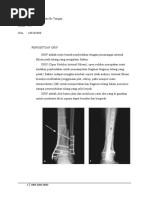

Vulnus laceratum atau luka robek terjadi akibat kekerasan benda tumpul yang menyebabkan robekan jaringan dan sering kerusakan organ di dalamnya, seperti patah tulang. Penyebabnya antara lain alat tumpul, jatuh ke benda tajam dan keras, kecelakaan lalu lintas, gigitan, atau kuku. Tanda dan gejalanya meliputi luka yang tidak teratur, jaringan rusak, bengkak, pendarahan, dan akar rambut yang tamp

Vulnus Laceratum